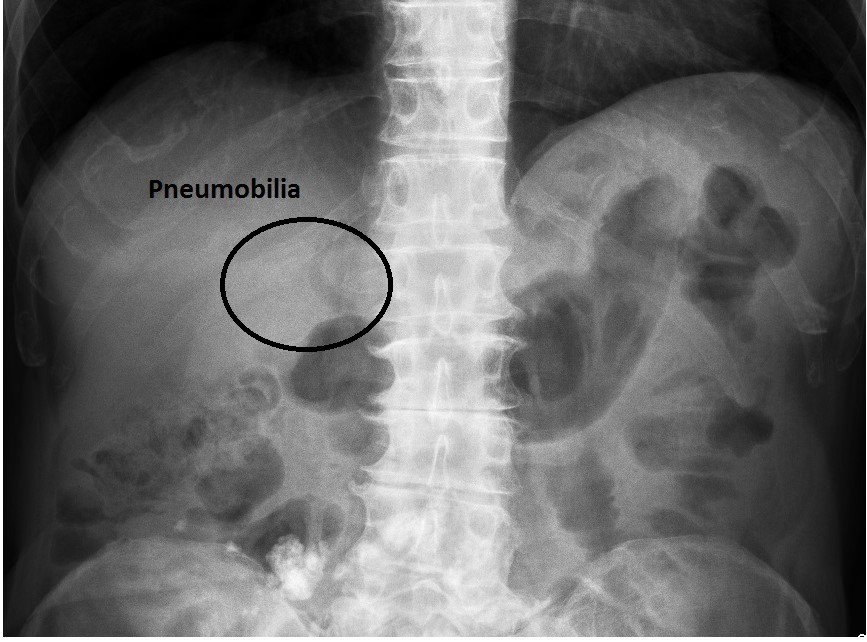

Khí đường mật [62 cases]

Danh mục: Tiêu Hóa